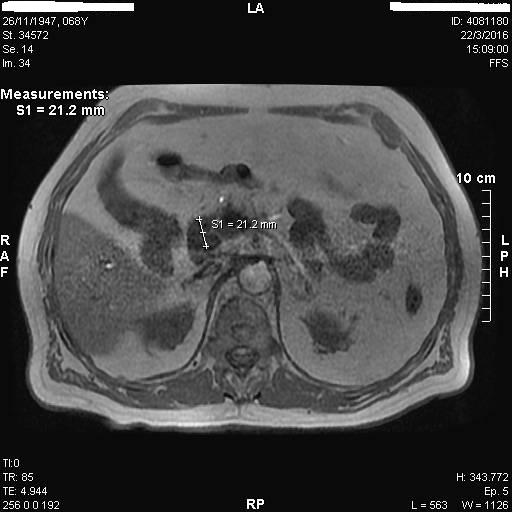

3) Νευροενδοκρινικός όγκος παγκρέατος (ινσουλίνωμα)

Άνδρας 71 ετών παρουσίαζε υποτροπιάζοντα επεισόδια υπογλυκαιμίας από 2ετίας. Είχε υποβληθεί σε λεπτομερή ορμονολογικό έλεγχο σε εξειδικευμένο ενδοκρινολογικό κέντρο που ήταν συμβατός με υπερπαραγωγή ινσουλίνης από πιθανό ινσουλίνωμα. Παρά ταύτα, ο απεικονιστικός έλεγχος με αξονική τομογραφία άνω-κάτω κοιλίας με λεπτές τομές (MDCT) και μαγνητική τομογραφία (MRI) κοιλίας δεν ανέδειξε τον όγκο. Ο ασθενής παραπέμφθηκε για έλεγχο του παγκρέατος με ενδοσκοπικό υπέρηχο (EUS). Ο ενδοσκοπικός υπέρηχος με linearενδοσκόπιο έδειξε ένα στρόγγυλο, υποηχοϊκό μόρφωμα, με ομαλή παρυφή, διαμέτρου μόλις 6 χιλιοστών στα όρια σώματος και ουράς του παγκρέατος. Δεν κρίθηκε σκόπιμο να γίνει βιοψία, αφού τα ευρήματα ήταν τυπικά ενός νευροενδοκρινικού όγκου. Το ινσουλίνωμα ήταν κοντά στην επιφάνεια του παγκρέατος και σε απόσταση από τον κυρίως παγκρεατικό πόρο. Συνεστήθη χειρουργική αφαίρεση με εκπυρήνιση του όγκου αλλά ο ασθενής προτίμησε να ακολουθήσει συντηρητική αγωγή με διαζοξίδη.